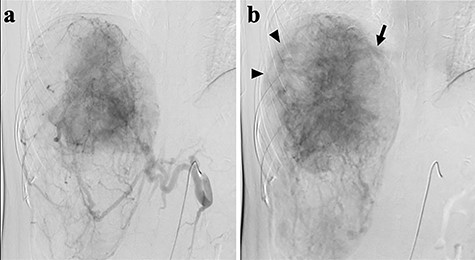

A 45-year-old woman was referred to our hospital with a huge liver tumor, which had been diagnosed as HAML 5 years previously when it was 12 cm in diameter (Fig. 1). Periodic follow-up with ultrasound and magnetic resonance imaging after the initial diagnosis had shown a progressive increase in the size of the tumor, and by the time of referral it measured 20 × 14 cm and had become symptomatic. On admission, enhanced computed tomography revealed a very large, well-defined, mixed-density mass occupying the entire right lobe of the liver (Fig. 2). Angiography showed dilated and tortuous vessel inside the tumor, and a drainage vein from the tumor to the right hepatic vein was visualized in the early phase (Fig. 3).

Abdominal angiography; (a) hepatic angiography shows a hypervascular tumor with a fine network of vessels in the arterial phase; (b) dilated and tortuous vessels (arrow heads) were noted inside the tumor, then a drainage vein to the right hepatic vein (arrow) was visualized in the early phase.